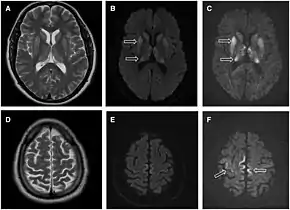

Imaging

Imaging of the brain may be performed during medical evaluation, both to rule out other causes and to obtain supportive evidence for diagnosis. Imaging findings are variable in their appearance, and also variable in sensitivity and specificity.[43] While imaging plays a lesser role in diagnosis of CJD,[44] characteristic findings on brain MRI in some cases may precede onset of clinical manifestations.[45]

Brain MRI is the most useful imaging modality for changes related to CJD. Of the MRI sequences, diffuse-weighted imaging sequences are most sensitive.[46] Characteristic findings are as follows:

- Focal or diffuse diffusion-restriction involving the cerebral cortex and/or basal ganglia. In about 24% of cases DWI shows only cortical hyperintensity; in 68%, cortical and subcortical abnormalities; and in 5%, only subcortical anomalies.[47] The most iconic and striking cortical abnormality has been called "cortical ribboning" or "cortical ribbon sign" due to hyperintensities resembling ribbons appearing in the cortex on MRI.[48] The involvement of the thalamus can be found in sCJD, is even stronger and constant in vCJD.[49]

- Varying degree of symmetric T2 hyperintense signal changes in the basal ganglia (i.e., caudate and putamen), and to a lesser extent globus pallidus and occipital cortex.[44]

- Cerebellar atrophy

| Signal hyperintensity in the caudate nucleus and putamen on diffusion-weighted and FLAIR MRI | Often present | Often absent |

| Pulvinar sign-bilateral high signal intensities on axial FLAIR MRI. Also posterior thalamic involvement on sagittal T2 sequences | Not reported | Present in >75% of cases |